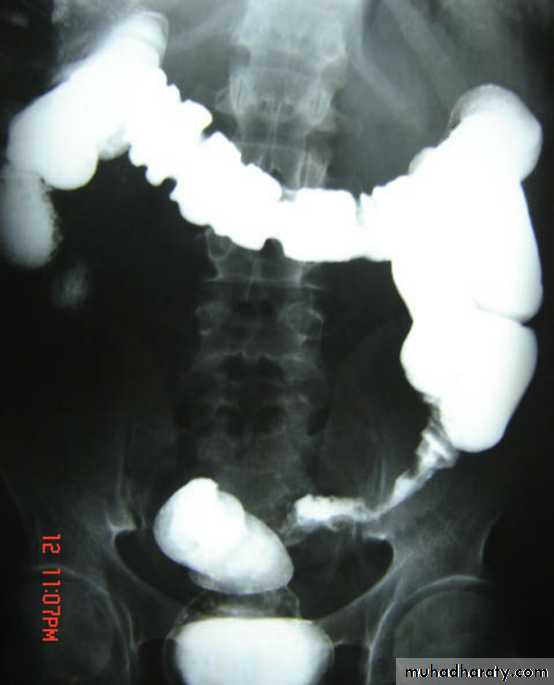

• Colonic Polyp:_Solitary or multiple._Produce small , well-defined rounded filling defect best seen in double contrast enema or post-evacuation enema ._ May be sessile or pedunculated ._ The pedicle appear as two parallel line of filling defect (stalk) and shows change of position with change of posture of patient .Familial adenomatosis polyposis syndrom (FAPS)

• The condition is familial .• Its a predesposition to colonic carcinoma .

• The colon shows multiple filling defects through out its length of different sizes.

• Imaging usually under estimates the number of polyps because most of them< 5mm in size .

• Signs of malignant changes can be seen.

colorectal CA

• Is the most common cancer of the gastrointestinal tract and the second most frequently diagnosed malignancy in adults.• Colorectal cancers can be found anywhere from the caecum to the rectum, in the following distribution :

• _recto-sigmoid: 55%

• _caecum and ascending colon: 20%

• _ileocaecal valve: 2%

• _transverse colon: 10%

• _descending colon: 5%

Multiple lesions are seen in the liver and spleen consistent with metastases